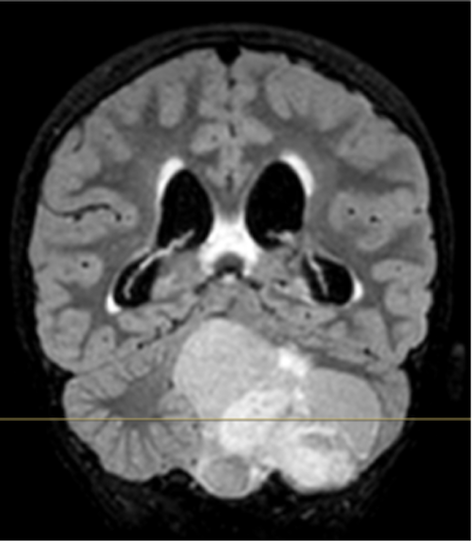

Infine, nei giorni successivi, il ragazzo si sottopone alla RM encefalo che documenta una voluminosa lesione espansiva in fossa cranica posteriore a partenza cerebellare sinistra con componente solida e cistica, idrocefalo triventricolare con segni di trasudazione ependimale (Figura).